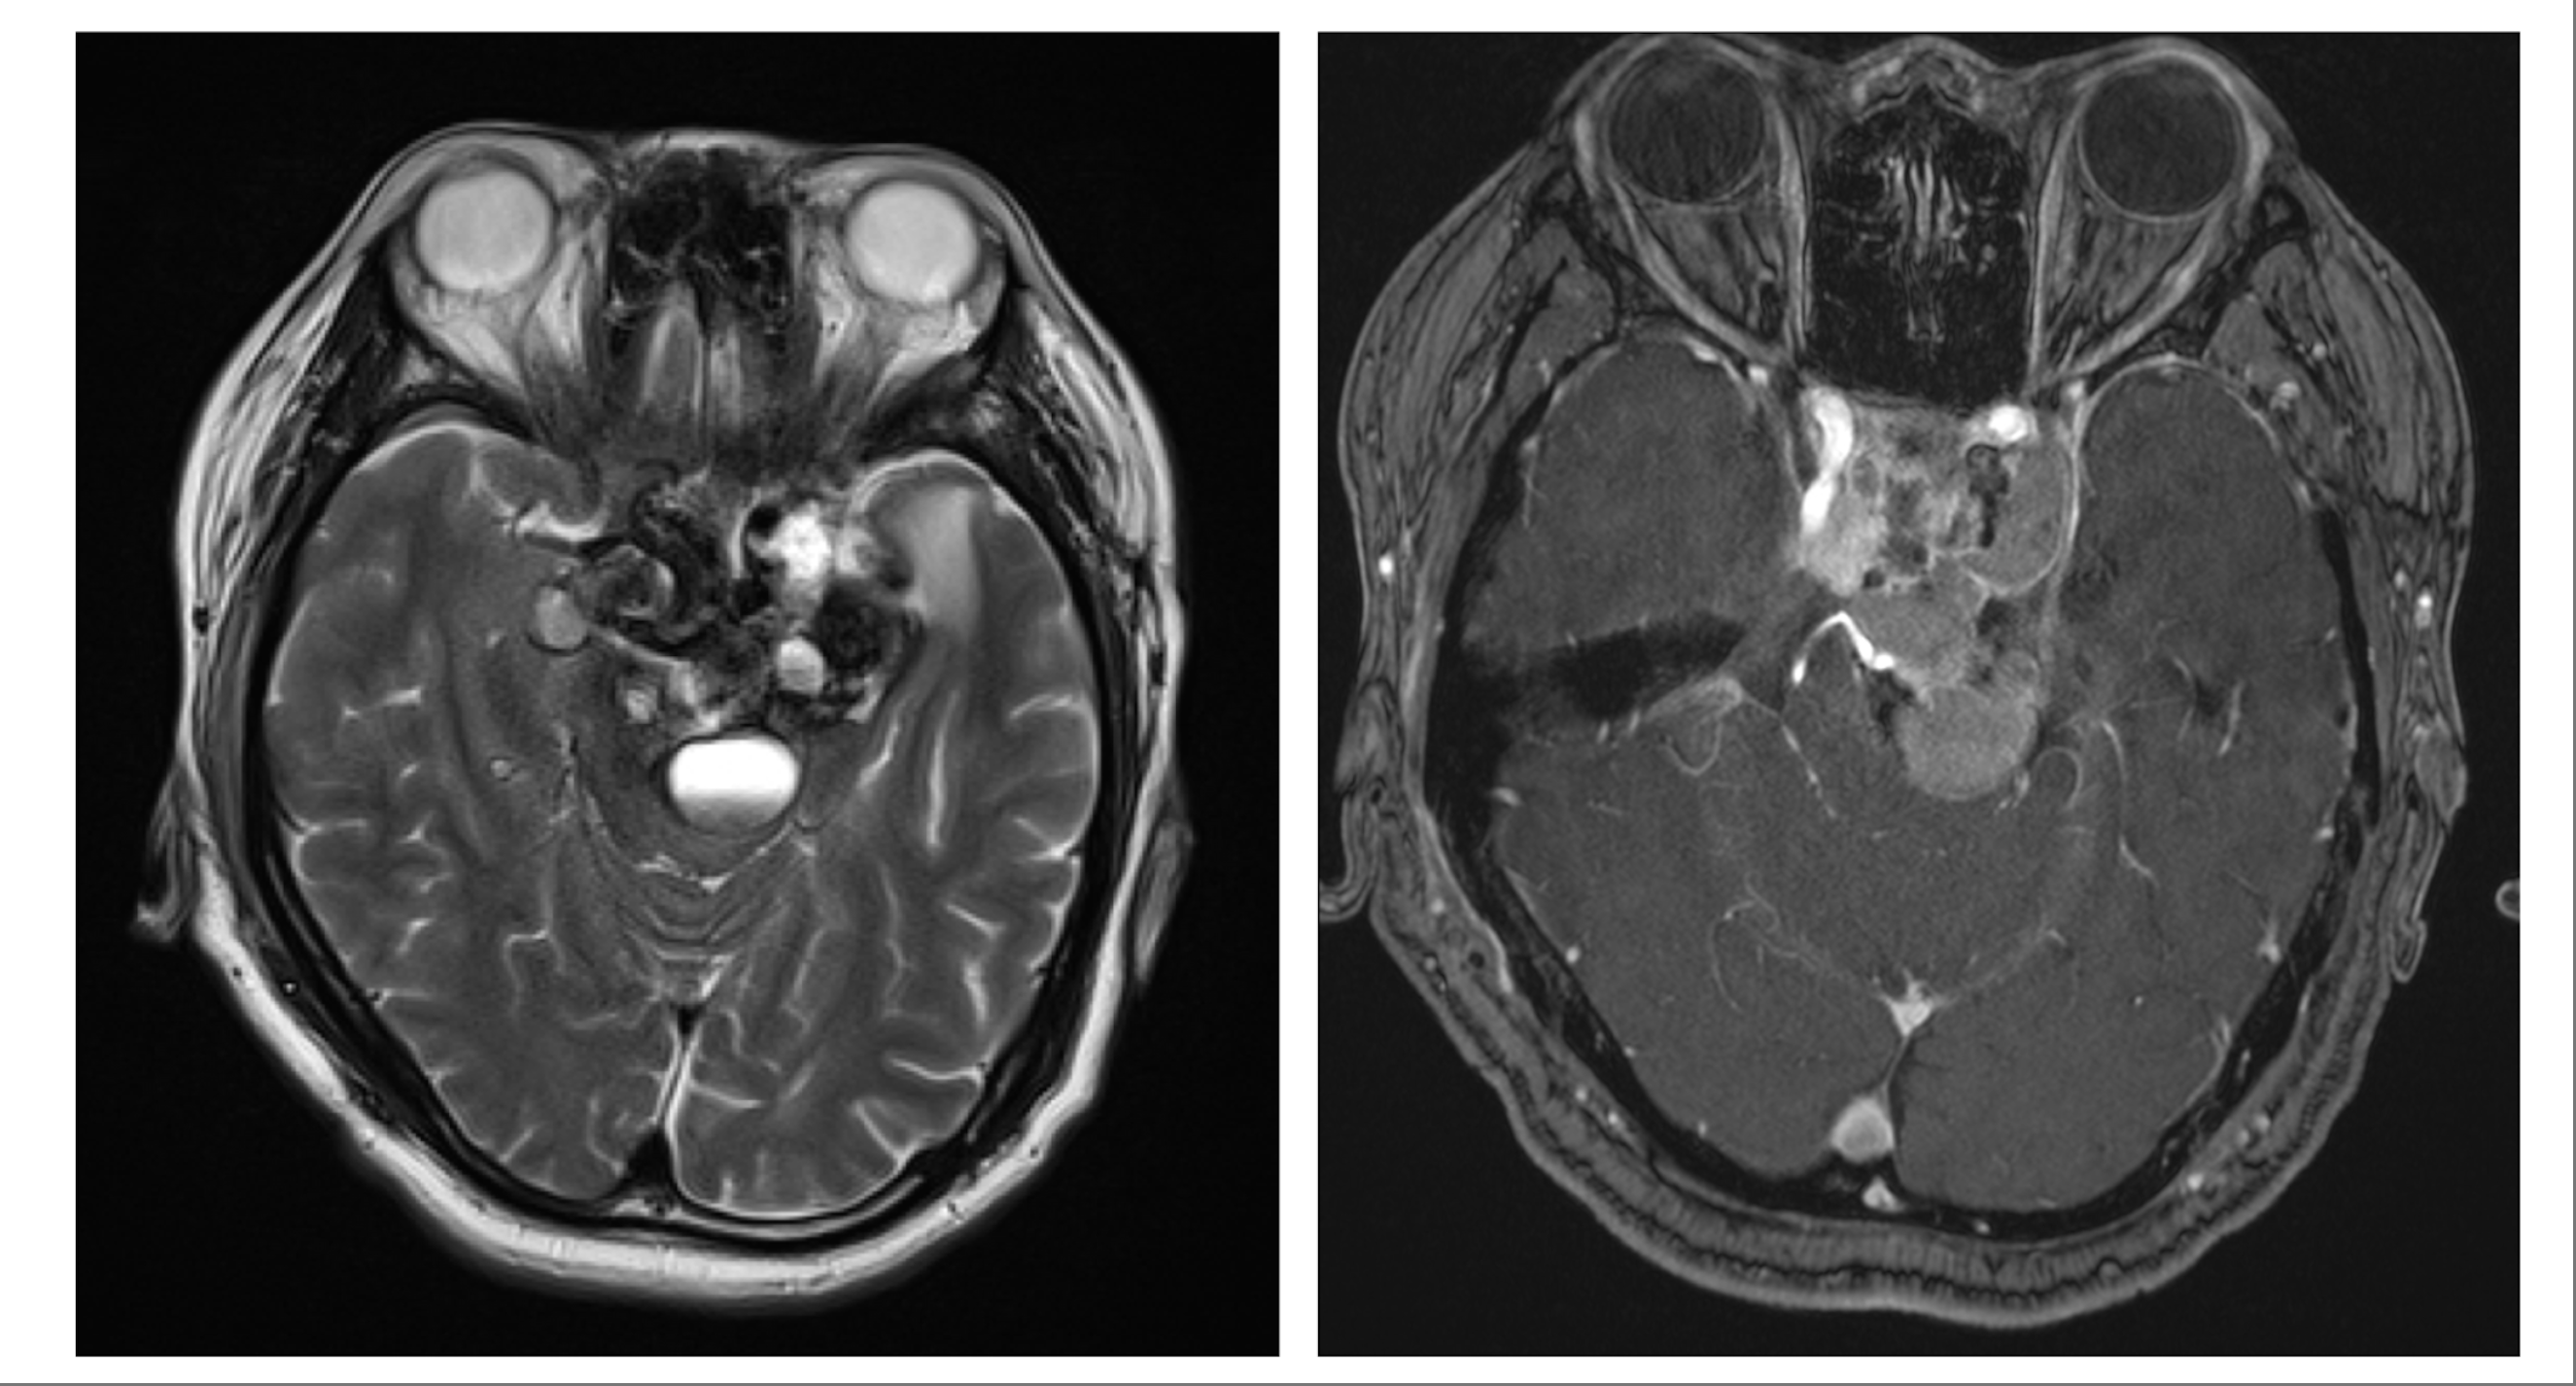

此外,顱底內窺鏡經眶手術還可用於術前診斷。麥凱鈞舉例說明,部分患者的顱底腫瘤位置狹窄,直徑僅約1厘米甚至數毫米,常規核磁共振(MRI)難以清晰顯示,此時需要提取腫瘤組織進行病理化驗。應用經眼眶手術後,團隊無需開顱,即可直接經眼眶精準取樣。他分享:「我有幾位患者通過這種方式取得組織,結果出乎意料——可以通過藥物等非手術方式治療。這對患者而言無疑是更好的選擇,因為無需再承受第二次手術。」

對於每一位前來求診的腦瘤患者,麥凱鈞醫生表示,首要任務是詳細講解病情,並告知患者不同的治療選項。他指出,顱底內窺鏡經眶手術只是其中一種方法,還有其他治療方案。因此,必須與患者講清楚不同療法的優缺點,隨後向病人講解手術的過程,「有時我會在磁力共振片,或者在一些模型上顯示給他看,告訴他這個手術是怎樣的。」